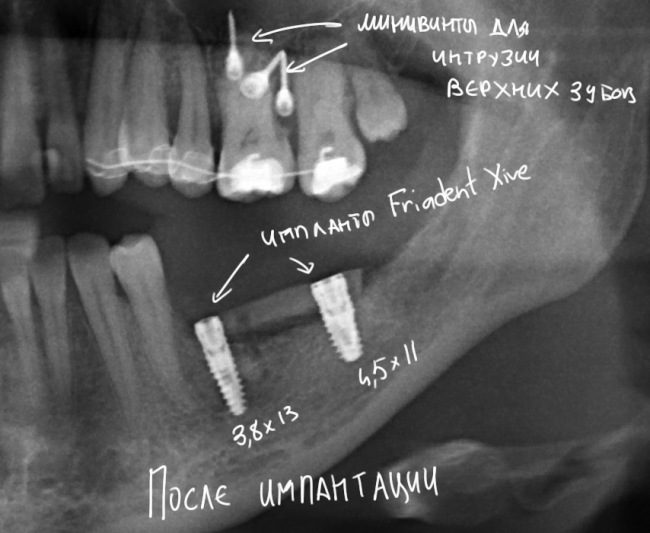

Снимок после проведенной имплантации:

после имплантации 2

Винты, фиксировавшие блок, удалены. Имплантаты позиционированы по разметке ортопеда, исходя из планируемой ортопедической конструкции.

Многих пациентов также интересует, как заживает тот участок челюсти, с которого был взят костный блок для пересадки. На снимке выше очень хорошо видно, что через три месяца костная ткань там почти полностью восстановилась — область забора блока еле видна.

Вот схема:

Sketch1051936

На верхней челюсти — микровинты в качестве кортикальной опоры, необходимой для интрузии зубов. Поскольку костная ткань верхней челюсти не очень плотная, и винты, как оказалось, не дают нужной поддержки, в дальнейшем планируем заменить их на микропластину.